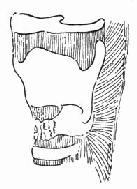

图96-15 环状软骨骨折

1.症状 急性声门下喉损伤为环状软骨骨折(图96-15),或有或无贯穿喉损伤。如果发现有环状软骨与气管间断裂也可按声门下损伤处理。

2.手术适应证 单独环状软骨骨折,环状软骨骨折同时并有贯通喉损伤,环状软骨骨折并有气管损伤(包括环状软骨和气管环间横断伤)都为此手术适应证。